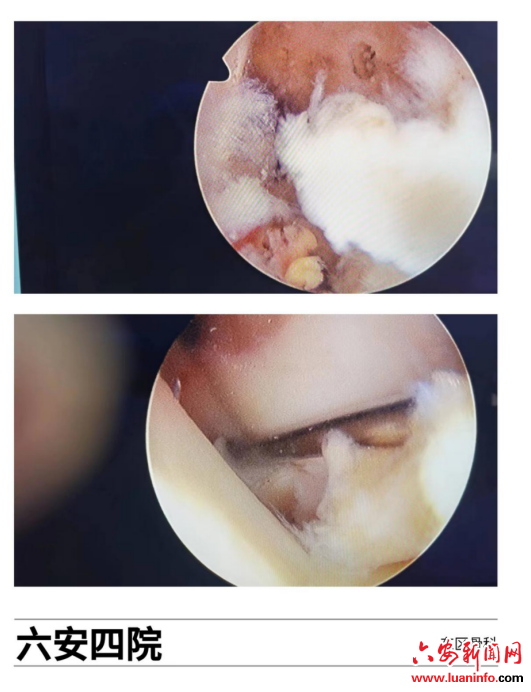

为缓解患者症状,使其膝关节功能得到有效恢复,综合患者病情,四院东区骨科团队经过周密术前讨论和规划,为患者制定了治疗方案,建议行膝关节镜下左前叉韧带重建+半月板缝合术,术中关节镜下探查明确后予取自体半腱肌+股薄肌肌腱重建前交叉韧带,同时发现左膝外侧半月板桶柄样撕裂,以半月板缝合器械行全内缝合,关节内清理完毕后在前交叉韧带定位器辅助下打好股骨及胫骨隧道,将台下编织好肌腱顺利牵引至关节腔内,股骨端以带袢钢板固定,胫骨端以挤压螺钉固定;手术结束,患者膝关节仅留一个3cm的取腱切口及三个0.5cm的微创切口;术后即刻予患肢伸直位支具固定,并膝关节冰敷、消肿镇痛、预防感染等处理;指导逐步行功能锻炼,现术后正处于功能恢复过程中,患者及家属对整个治疗过程非常满意。